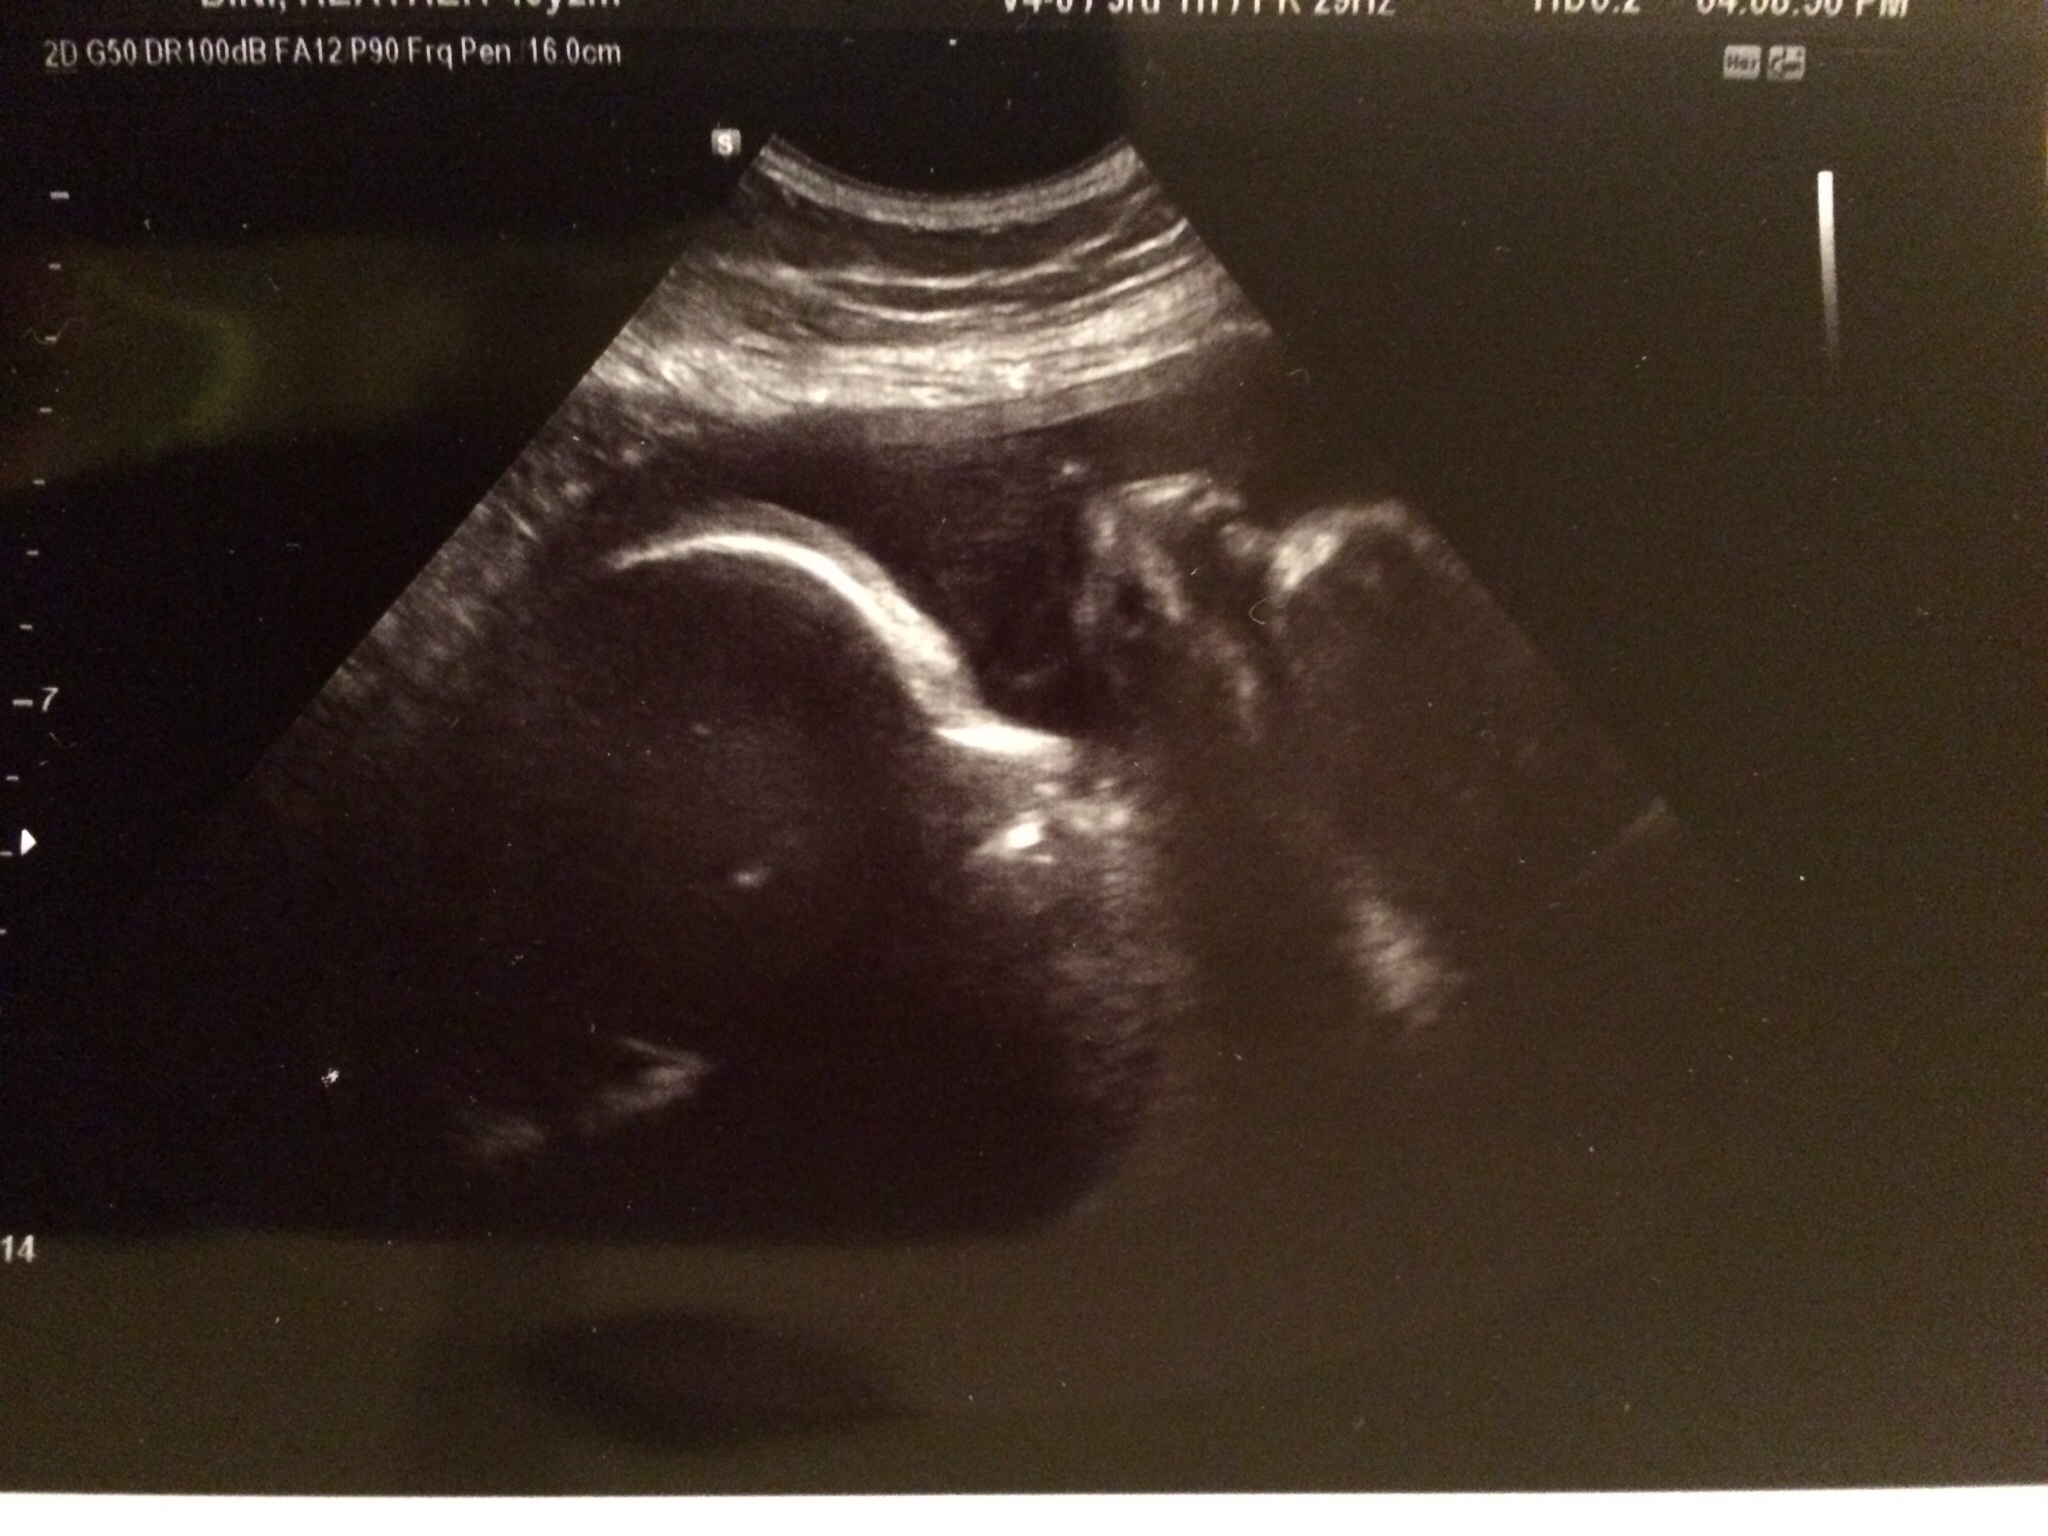

So today I was seen at about 1030 for another ultrasound. This was kind of nice because I had an ultrasound tech and she let me see Skippy's face -- BIIIIIG yawn, so cute! -- before looking at the important bits--her heart. And she gave me some pictures. Of course, the arrhythmia showed up so she went and got the doctor so he could take a look. He looked at her heart and watched the arrhythmia for a while and said the same thing everyone else has been saying. But he added that if it doesn't resolve by the time I go into labor, they can't usually tell how the baby's heart is handling labor, which leads to c-section... But he said that was unlikely. ? I don't know.

Had US all seems good. Didn't get great US pics since she is still breech. Her is facing me. Was so hoping she would turn by now. She is 4.5 pounds 16 in long and HR 129. I am huge but all belly. She is big too!!! I go back in 4 weeks. I so hope she turns by then.

2 nd pic are pics of her feet!!!